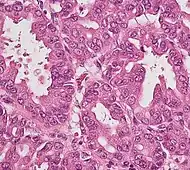

Micrographs of normal pancreas, pancreatic intraepithelial neoplasia (precursors to pancreatic carcinoma) and pancreatic carcinoma, H&E stain

The first is pancreatic intraepithelial neoplasia (PanIN). These lesions are microscopic abnormalities in the pancreas and are often found in autopsies of people with no diagnosed cancer. These lesions may progress from low to high grade and then to a tumor. More than 90% of cases at all grades carry a faulty KRAS gene, while in grades 2 and 3, damage to three further genes CDKN2A (p16), p53, and SMAD4 – are increasingly often found.[2]